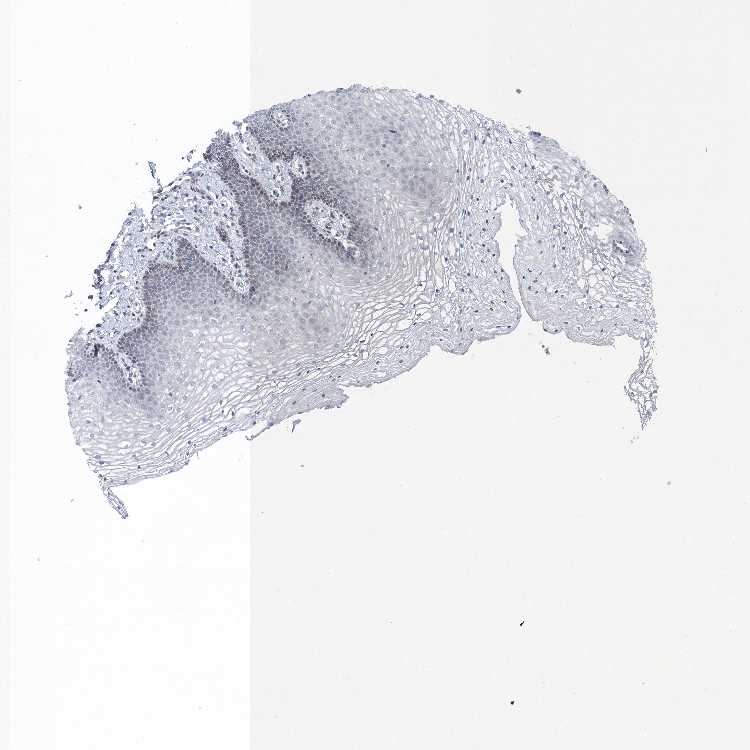

TISSUE PRIMARY DATA VAGINA Show tissue menu

VAGINA - Antibody stainingi

Antibody staining in the annotated cell types in the current human tissue is reported as not detected, low, medium, or high, based on conventional immunohistochemistry profiling in selected tissues. This score is based on the combination of the staining intensity and fraction of stained cells.

Each image is clickable and will lead to virtual microscopy that enables deeper exploration of all samples and also displays staining intensity scores, fraction scores and subcellular localization as well as patient and tissue information for each sample.

Antibody HPA041504

Squamous epithelial cells Not detected